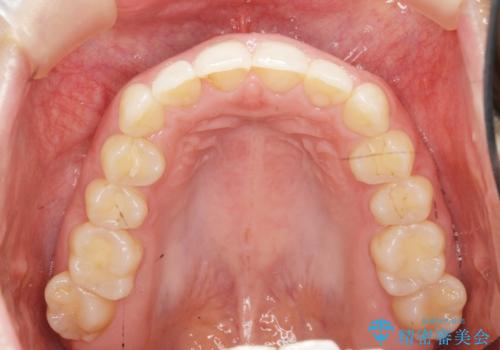

前歯のガタつきをきれいに マウスピース矯正治療

- 「前歯のガタつきをきれいにしたい。」と矯正治療を希望され来院されました。

前歯のガタつきをワイヤー部分矯正、上顎前突の咬合関係を後方移動することで理想的な咬合関係を確立します。

上顎の全体的な後方移動を実現するためにマイクロインプラントを併用したゴムかけを行ったことで理想的な咬合関係を確立することができました。